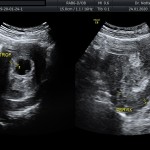

- Trofoblasto (posibles desprendimientos)

- Cérvix uterino y anexos

Este estudio generalmente es realizado por vía trans vaginal, sin embargo, cuando las condiciones de exploración ecográfica son adecuadas se puede realizar por vía abdominal.